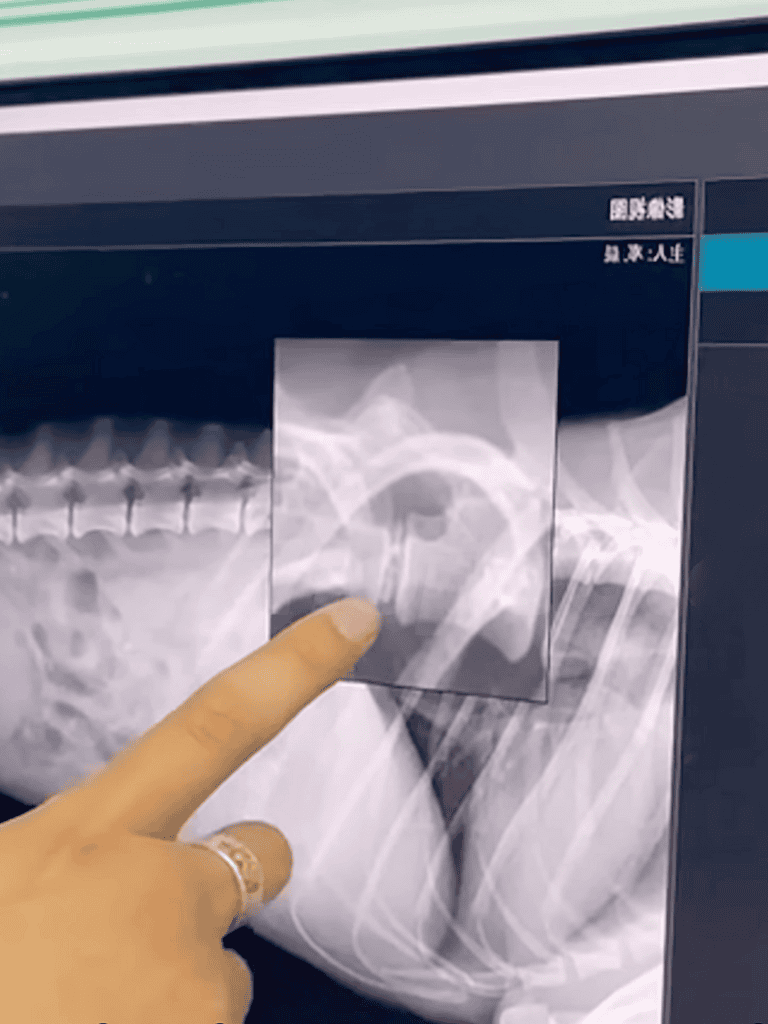

The doctor examined Tiao Tiao, his hands moving along the dog’s frail spine.

“We don’t yet know if his lumbar spine is dislocated,” he said. “An X-ray will give us a clearer picture.”

The doctor returned with the X-ray results, his expression unreadable. He motioned for me to come closer and pointed at the images, explaining Tiao Tiao’s condition. My heart pounded as I tried to absorb his words, bracing for the news.

During the examination, the doctor noted an unusual growth on Tiao Tiao’s waist, possibly a bone spur or hyperplasia. It had left his hind legs without sensation, complicating his condition.

Tiao Tiao’s hind legs were numb due to spinal nerve compression. The doctor pointed to the X-ray, explaining its severity. Tiao Tiao lay still, unaware of his condition. I refused to give up hope.